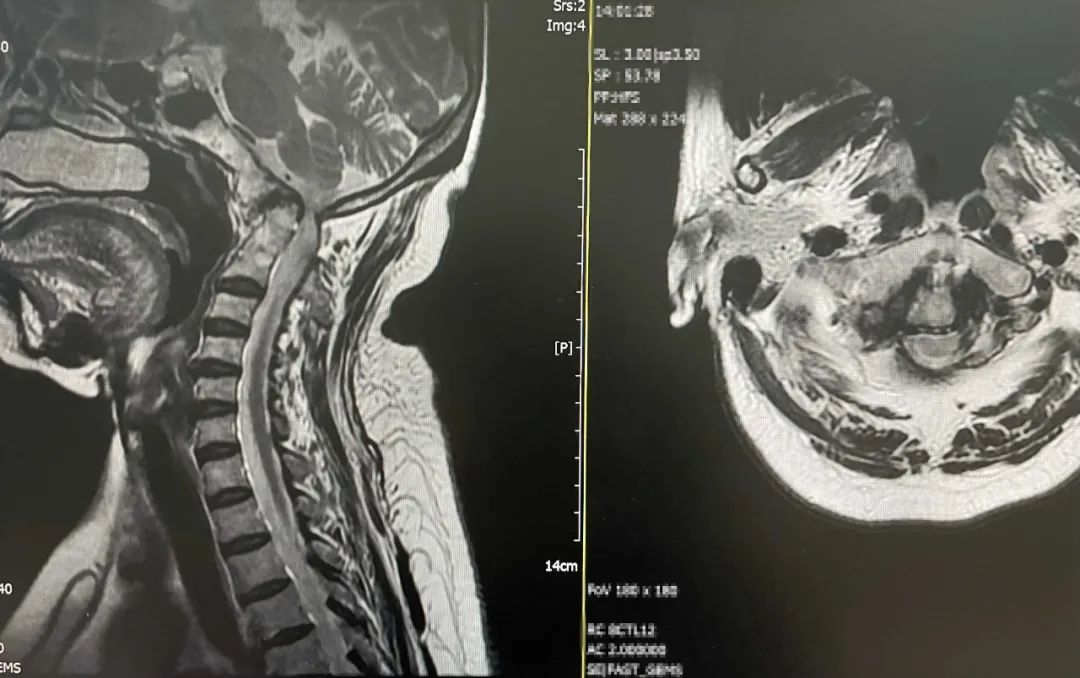

患者女性,63岁,不久前不慎摔伤,头部着地后当即颈项部疼痛,伴四肢麻木无力,随后到我院门诊脊柱外科就诊,入院时呈现不全瘫状态,四肢肌力差,左侧肢体肌力减退明显,双上肢感觉减退,无法正常行走,经常性头晕头痛,生活质量差。入院后经详细查体及影像学检查,发现该患者患有颅底凹陷症并颈脊髓缺血,寰枕先天性融合畸形、枢椎与颈3锥体先天性融合畸形、双侧额叶散在小缺血灶、右椎动脉先天性发育纤细,病情复杂。

▲术前MRI